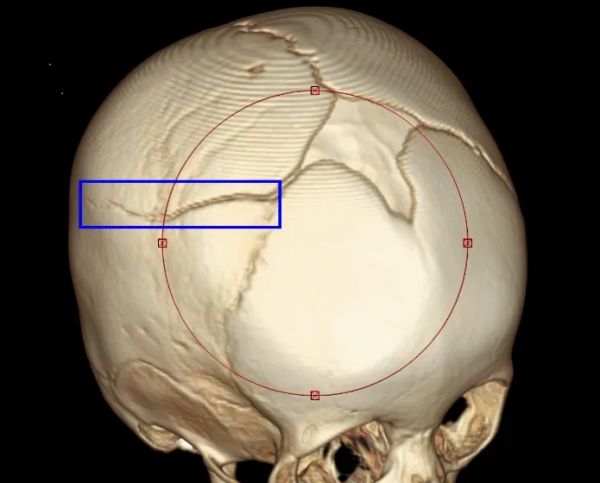

這名11個月的寶寶被撞後,當場昏迷,醫院檢查發現其顱骨骨折(圖中藍色區域)、顱內大面積出血,傷勢已經危及生命。

所幸經過神經外科醫生全力搶救,孩子的生命得以保住。